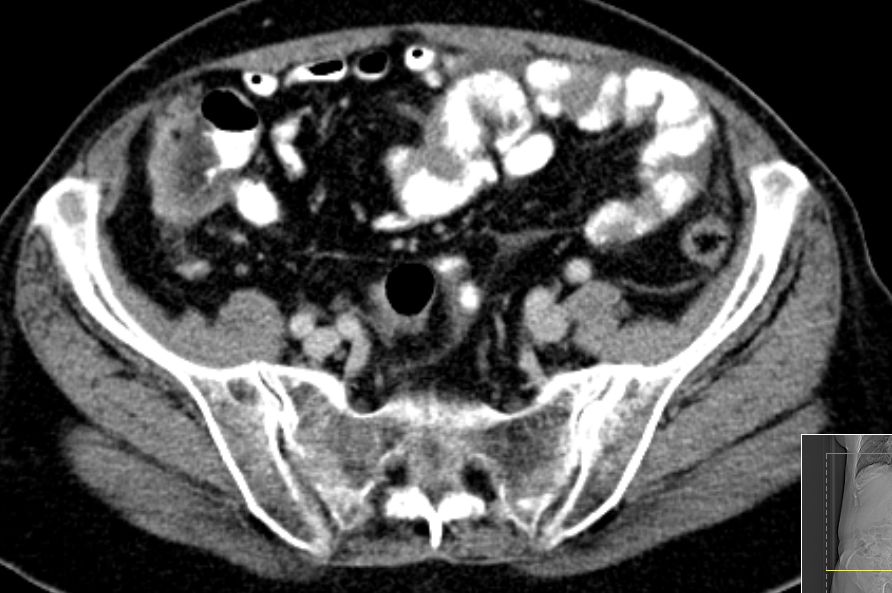

72-jährige Frau mit Peritonealkarziose nach HE mit

Adnexen vor 16 Jahren.

Histologie: Low-grade-serös-papilläres Karzinom

Intraoperatv ausgedehnte Karzinose der Darmserosa und des

Mesenteriums.